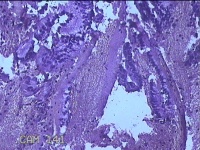

性别

女

年龄

44岁

临床诊断

子宫异常出血;子宫肌瘤;子宫内膜息肉

一般病史

阴道流血1月。

标本名称

宫颈管内膜

大体所见

纱布一块,内有灰白暗红色不规则碎组织1.5x1x0.2cm一堆。

图1